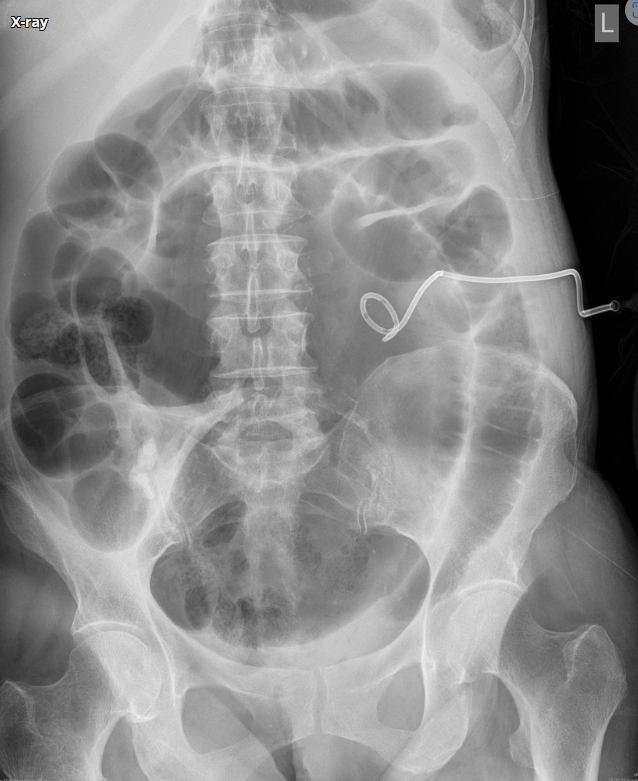

72세 남성이 복통과 지속적인 구토를 호소하며 병원에 내원하였다. 신체 검진에서 복부는 뚜렷하게 팽만되어 있었고, 혈압은 135/85 mmHg, 맥박은 102회/분, 호흡수는 20회/분, 체온은 36.8°C로 측정되었다. 복부 방사선 사진을 찍었다. 이 환자의 진단은 무엇인가?

Imp: Sigmoid volvulus

고령에서 복통, 구토, 복부 팽만감이 나타나고 있으며, AXR에서 Coffee bean sign으로 특징적인 구불결장꼬임증의 소견이 나타나고 있다. 치료는 직장의 감압(직장관 삽입 등), 원인 교정을 위한 추후 elective operation 등을 고려할 수 있다.

검사 | (1) 복부 X선: 커피콩 모양이 뚜렷하게 보임(coffee-bean sign) (2) 복부 CT: Mesentery가 소용돌이처럼 꼬인 모습(mesenteric whirl) |